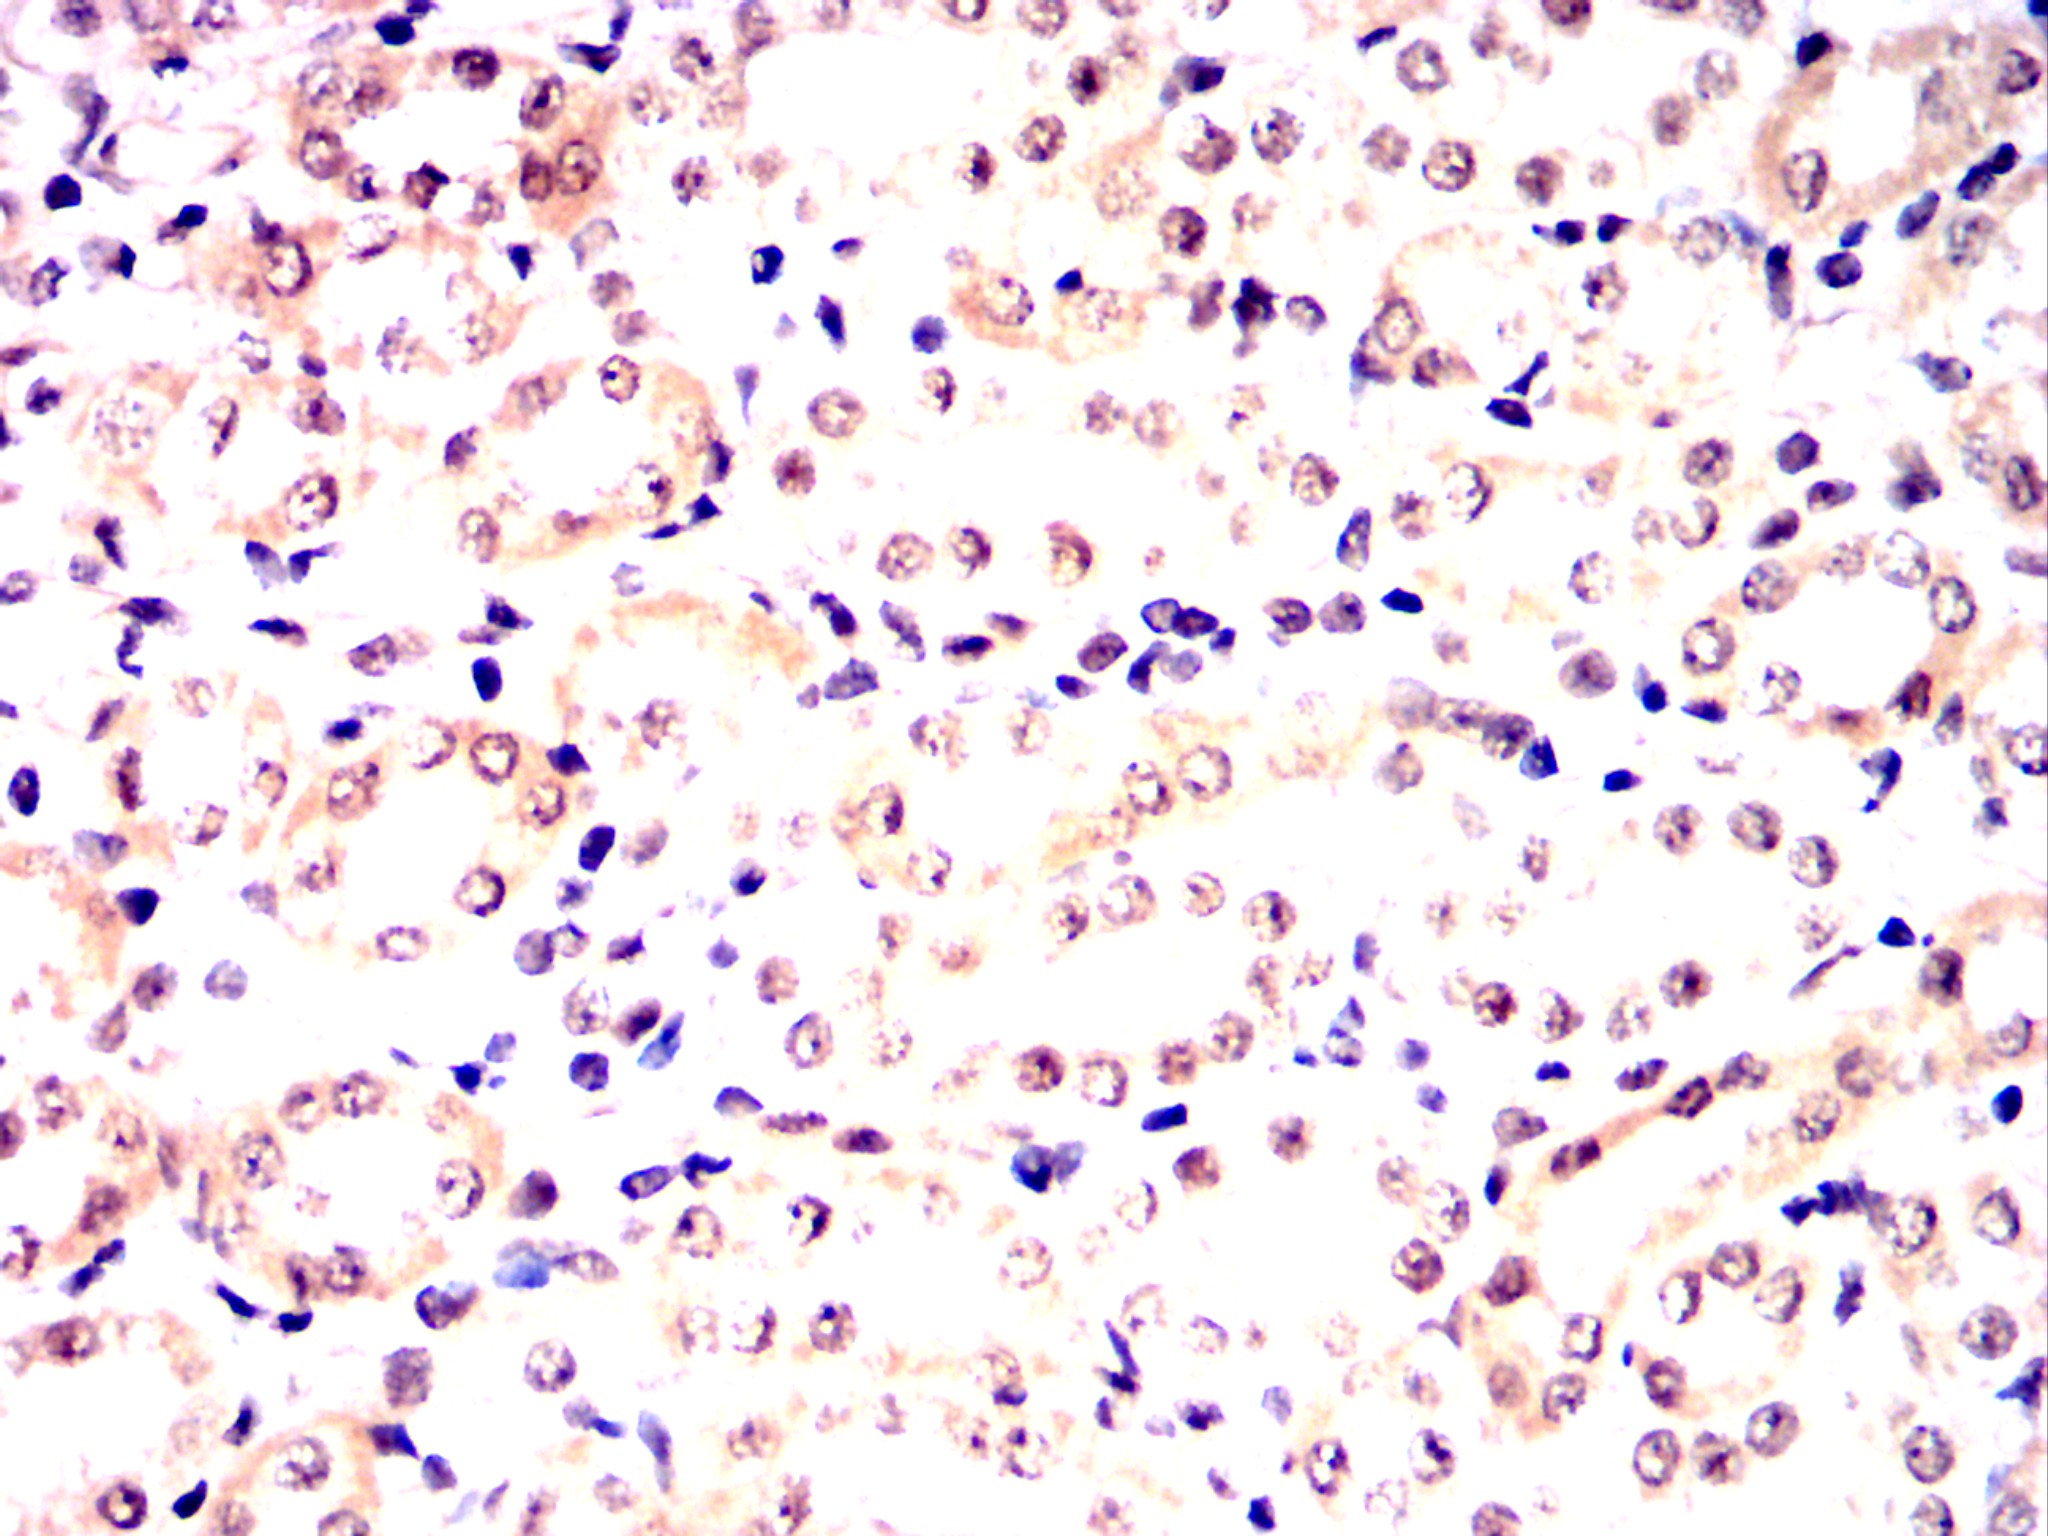

Immunohistochemical analysis of paraffin-embedded Rat kidney using OTX2 mouse mAb with DAB staining.

Immunohistochemical analysis of paraffin-embedded Rabbit kidney using OTX2 mouse mAb with DAB staining.